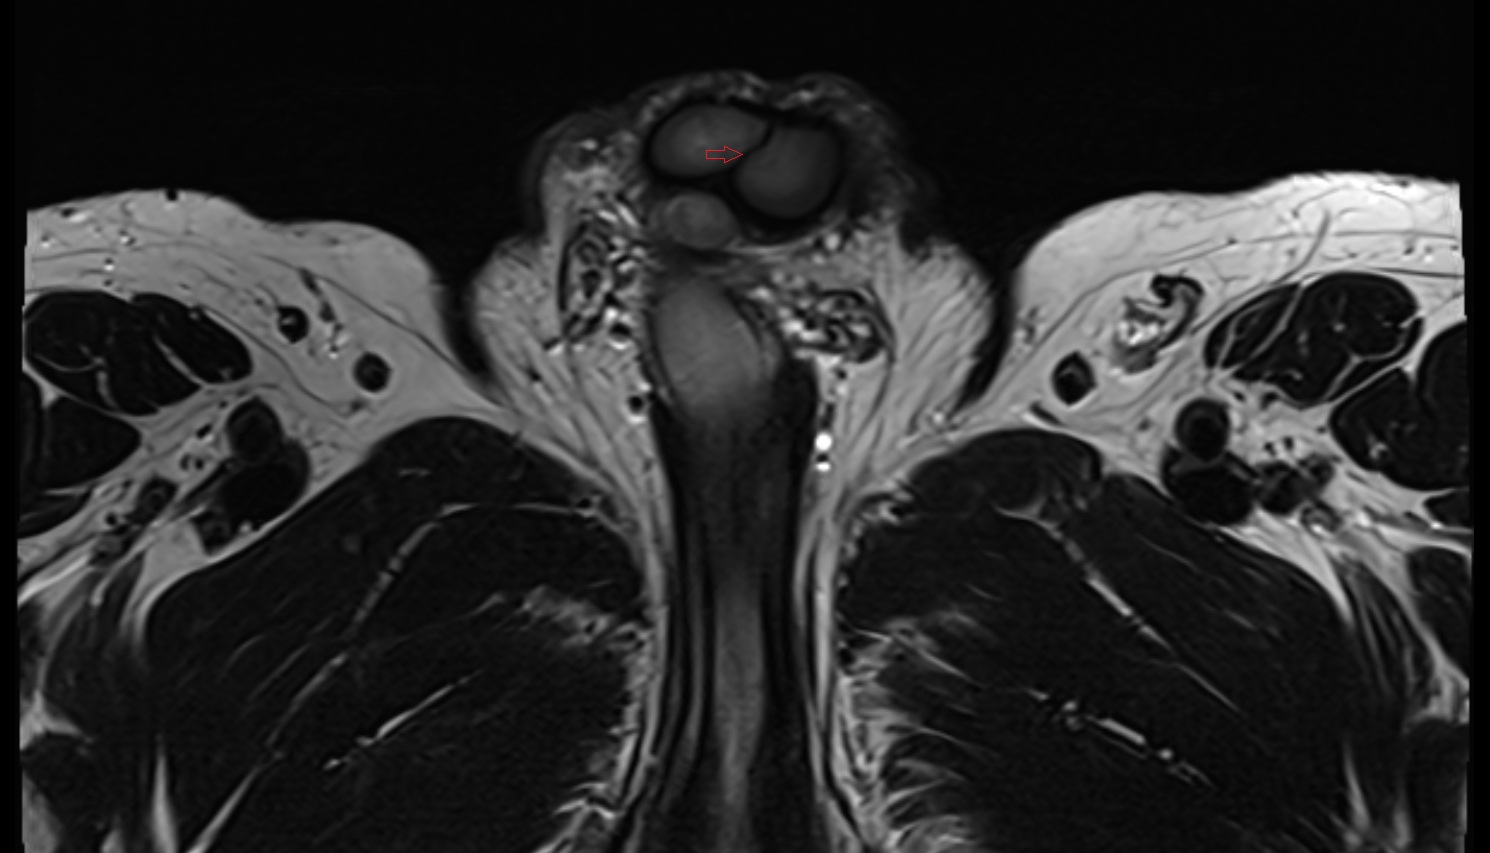

- Peripheral zone of prostate

- Anterior Fibromuscular Stroma of prostate

- Central zone of prostate

- Transitional zone of prostate